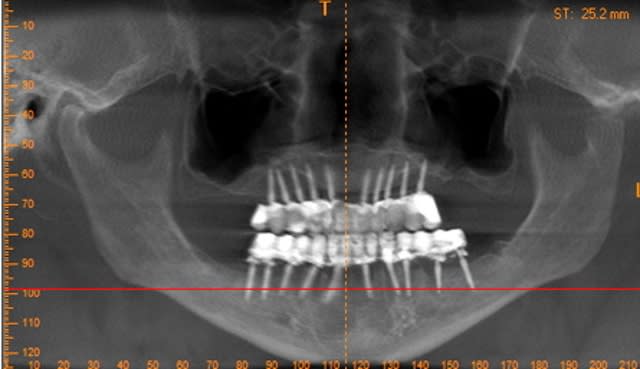

voici un cas extraction, implantation immédiate, mise en charge à 1 jour.

photo1:cas initial paro, mais os résiduel d'un bon volume.

photo2:pano

photo 4:pose de 6 implants evl compacts 4/12 (serf). Tous à plus de 45N, sauf en 36...

photo 5: le lendemain, transvissé pret ( on evite 36, pour le laisser tranquille)

photo 6: aspect à 1 jour.

photo 7: transvissé, vissé!

ce fut une grosse matinée, car le curetage fut long et minutieux, ainsi que le modelage des rebords alvéolaires...